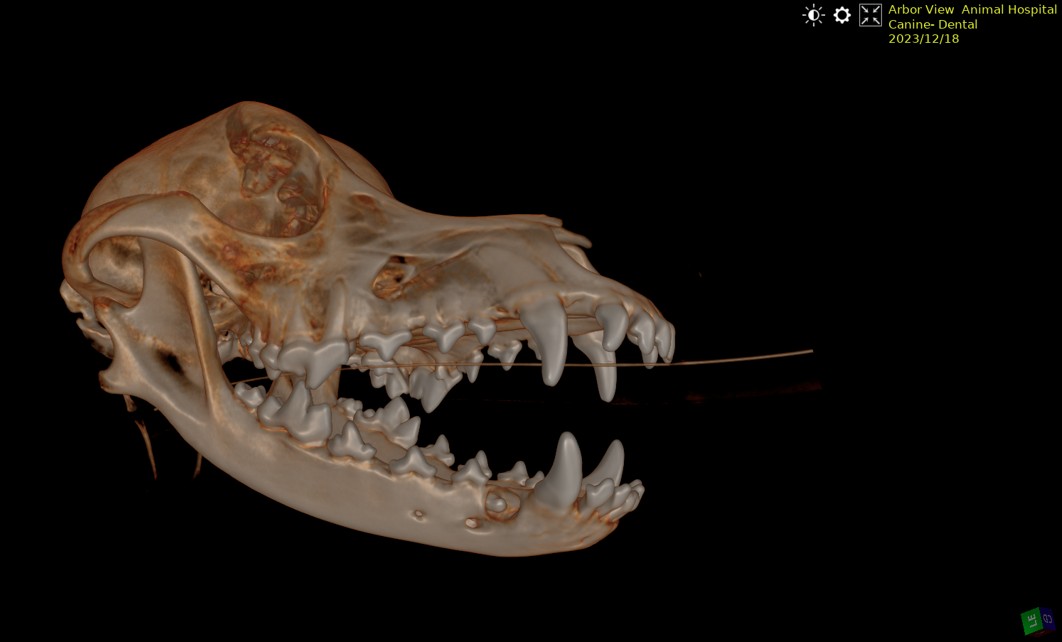

- Dental abscesses

- CT

This allows many patients to receive comprehensive evaluation and treatment without immediate referral to a specialty center.

In some urgent situations, pets may require surgical treatment or hospitalization. Conditions such as intestinal foreign body obstructions, bladder stones, pyometra (uterine infection), mass removal, or other acute medical concerns may need prompt surgical intervention.

Because Arbor View Animal Hospital is a full-service veterinary hospital, diagnostic testing, advanced imaging, anesthesia, and surgical care can often be coordinated in one location. Our goal is to provide efficient, compassionate care and minimize delays when timely treatment is important.